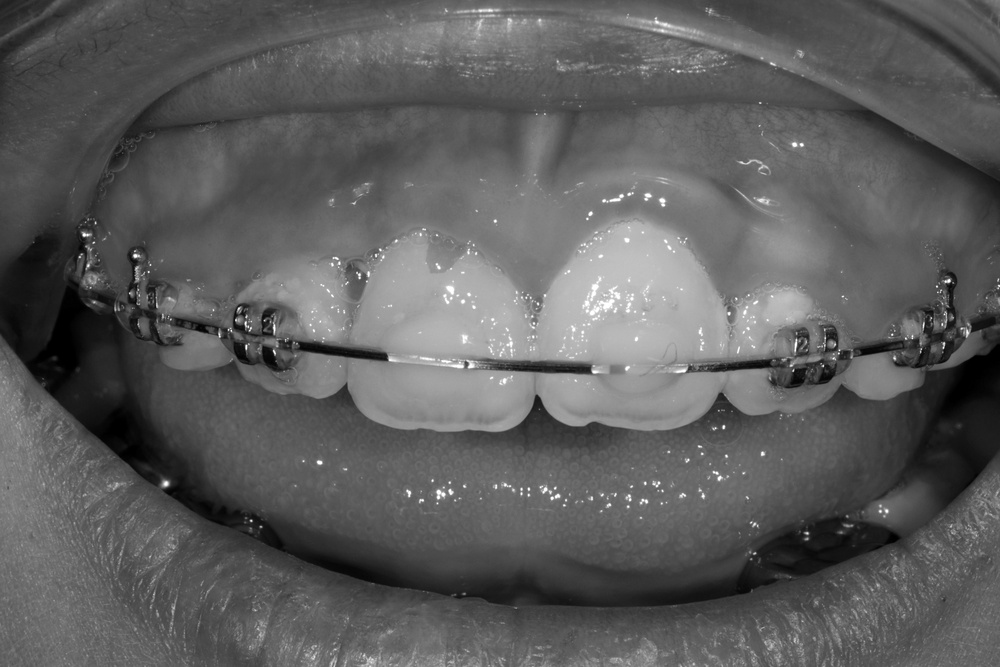

앞니가 비뚤게 나서 교정하러 온 친구입니다.

입천장의 고정식 확장장치를 이용해 좌우로 벌려서 치아를 배열할 공간을 만들었습니다.

그런데 친구가 학교에서 부딪혀서 다쳐 왔습니다.

바로 처치(치아를 철사로 부목 고정)후 신경치료를 진행하였습니다.

이후 치아배열을 마무리하여 가지런한 이를 가지게 되었습니다.